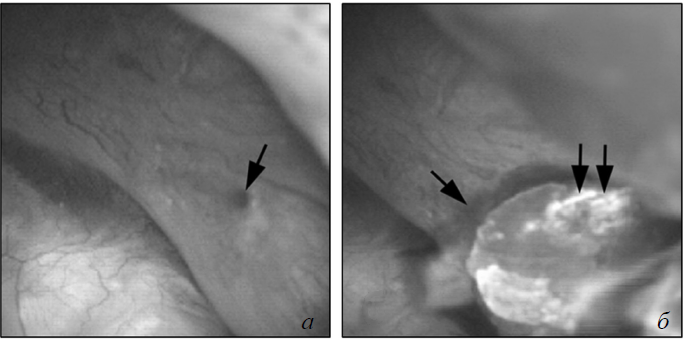

Неприкрепленные микролиты в дилатированных ВМСК можно было наблюдать вплоть до настоящего времени только при цистинурии (рис. 8). Микролиты цистина около 1–2 мм в диаметре могуть присутствовать в дистальных концах ВМСК и легко удаляются лазером (см. рис. 8, а, б).

Рис. 8. Эндоскопическое вскрытие внутренних медуллярных собирательных канальцев с удалением протокового конкремента у пациента с цистинурией: а) в дистальных концах внутренних медуллярных собирательных канальцев находятся цистиновые микролиты, легко определяемые во время ретроградной нефролитотрипсии под уротелием, и выглядят как затемнение (стрелка) в области расширенного протока; б) лазерное рассечение выводного отверстия канальца приводит к легкому вымыванию микролитов из просвета внутренних медуллярных собирательных канальцев

Протоки Беллини могут быть закупорены цистиновыми кристаллами, но без крепления заглушек к канальцам, поэтому эти заглушки могут быть удалены без особых усилий, и при этом эпителий остается неизмененным [11]. Это отличает их от прочих заглушек протоков Беллини. Так как они круглые и не прикреплены к стенкам канальцев, то формирование в свободном растворе очевидное объяснение для камнеобразования при цистинурии.